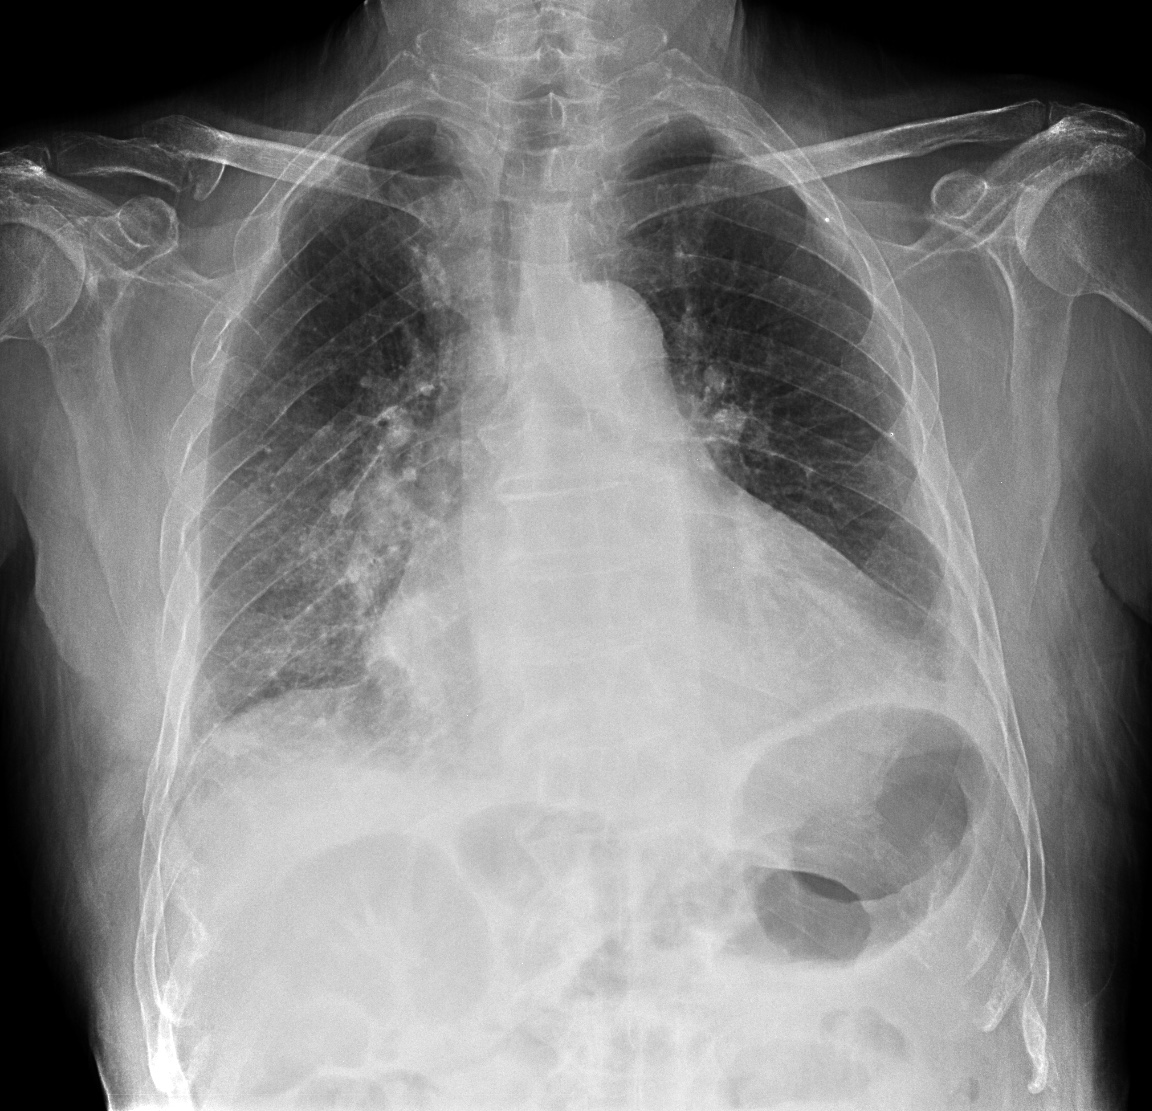

CASO: Operada de esofaguectomia y reconstrucción con coloplastia hace 3 meses. Sintomas de neumonía.

Hallazgos:

- De inicio llama la atención una densidad practicamente total del todo el hemitórax izquierdo, lo cual podría hacernos pensar que estamos ante una posible neumonía.

- Sin embargo el tórax está no está bien centrado, observar como la clavícula izquierda se encuentra casi en la mitad del pulmón, por tanto lo que vemos blanco es el mediastino ya que el tórax está rotado.

CENTRAJE:

El correcto centraje se determina comprobando que las extremidades internas de ambas clavículas equidistan de las apófisis espinosas vertebrales.

Mismo paciente, al cual esta vez se le ha tomado una radiografía en PA y en sedestación. Observar como las clavículas están equidistantes a las apófisis espinosas y como ha desaparecido el velamiento del pulmón izquierdo.

Por otra parte, paciente presenta una cardiomegalia y un discreto ensanchamiento del mediastino es probable relación con cambios postquirúrgicos.